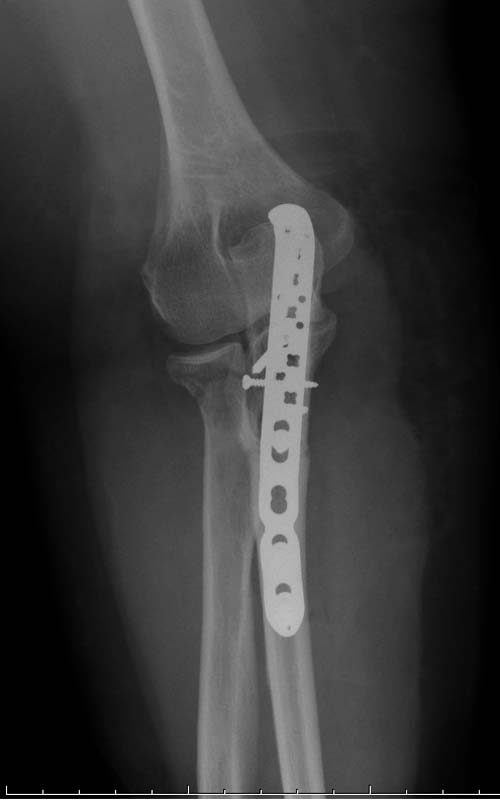

Здесь представлены несколько случаев и как видно больше больных с

серьезными повреждениями, чем изолированные..

отростка, Второй случай, заменена на протез, и третий, кроме фиксации

головки - реконструкция capitellum латерального мыщелка.

Вложение не в текстовом формате было извлечено…

Имя     : 5 Radial head EUA CRM.jpg

Тип     : image/jpeg

Размер  : 27336 байтов

Описание: отсутствует

Url     : http://weborto.net:8080/pipermail/ortho/attachments/20131119/c3543de4/attachment-0011.jpg